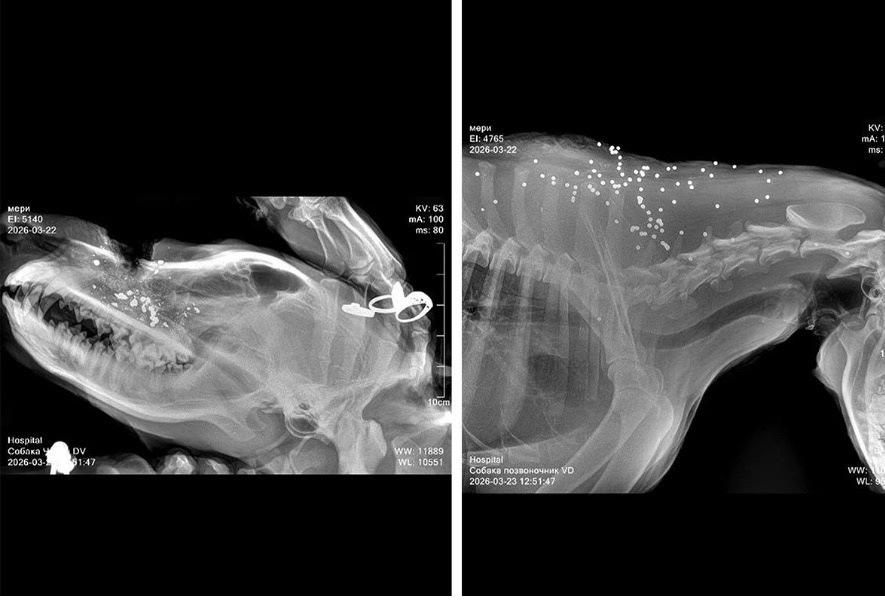

Одна собака погибла на месте. Ещё три — ранены. Одну успели доставить в ветклинику. У неё огнестрельные ранения дробью. Врачи борются за её жизнь. Две раненые собаки убежали. Куда — неизвестно. Выжили ли они тоже никто не знает.

Дробь на снимке